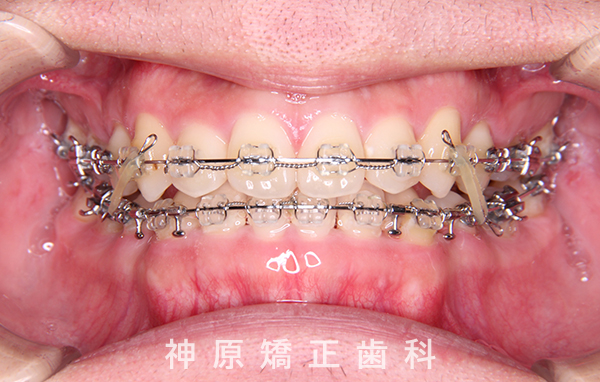

マルチブラケット装着1年後